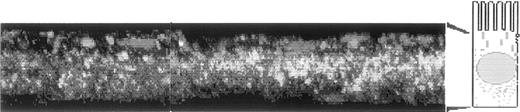

Optical slicing in the z-axis permitted localization of vesicles inside cells at different levels. Figure 1shows the distribution of Texas Red–labeled Fe-Tf (Figure 1A) and apo-Tf (Figure 1B) relative to the green ToPro-1–stained nuclei. The images have been reconstructed to allow examination from a lateral perspective. The distribution of vesicles containing apo-Tf is different from those containing Fe-Tf: apo-Tf appears in a perinuclear region and Fe-Tf in a more basal region. A similar pattern was seen when cells were incubated simultaneously with apo-Tf–Texas Red and Fe-Tf–Bodipy (data not shown).

Caco-2 cells grown in monolayers were incubated in the basal chamber with either 0.1 μm apo-Tf–Texas Red or 0.1 μm Fe-Tf–Texas Red for 20 minutes. The cell layers were washed and processed, and the nuclei were stained with ToPro-1 and examined by confocal microscopy as described in materials and methods. Figure 1A represents the incubation with Fe-Tf and Figure 1B the incubation with apo-Tf. In both panels, the images have been reconstructed to allow examination from a lateral perspective. The lateral view (xz) is made up by the addition of consecutive pixels in the y-axis (total of 1 μm). The nuclei are stained green. The cartoon next to each image depicts the approximate height of the cells in the reconstruction.

Distribution of apo-Tf–Texas Red and Fe-Tf–Texas Red in Caco-2 cells.